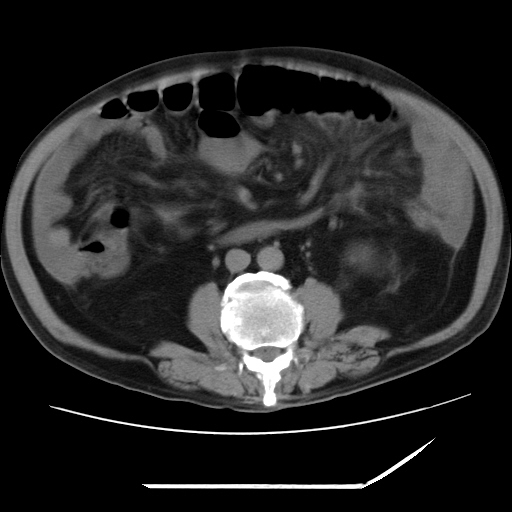

以下是引用zxl51642在2009-8-12 18:55:00的发言:[br]1、肠系膜脂肪浑浊,密度增高,腹水,支持腹膜炎诊断;2、右肾盂及输尿管中段结石,左输尿管起始段结石;3、胆囊切除术后改变?4、双侧胸膜腔少量积液;5、胰腺体积不大,勾勒清楚,肾前筋膜无增厚,不支持胰腺炎,请结合血尿淀粉酶及临床。

以下是引用黑白光影在2009-8-12 22:06:00的发言:[br][quote]以下是引用zxl51642在2009-8-12 18:55:00的发言:[br]1、肠系膜脂肪浑浊,密度增高,腹水,支持腹膜炎诊断;2、右肾盂及输尿管中段结石,左输尿管起始段结石;3、胆囊切除术后改变?4、双侧胸膜腔少量积液;5、胰腺体积不大,勾勒清楚,肾前筋膜无增厚,不支持胰腺炎,请结合血尿淀粉酶及临床。